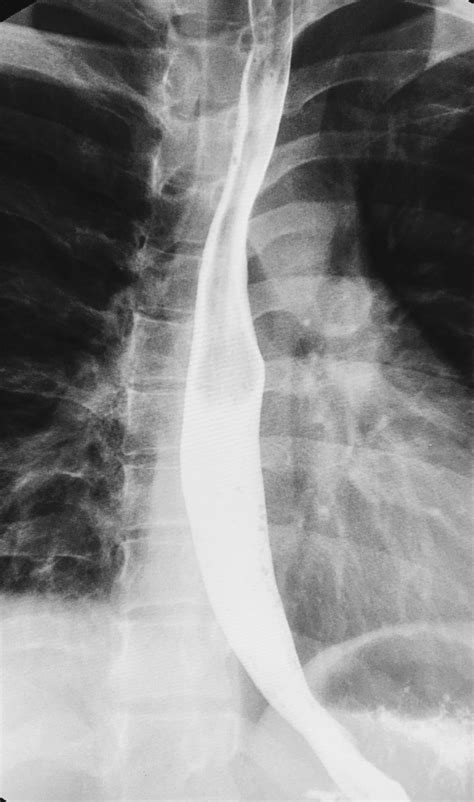

A Barium Swallow Test is essentially a "movie" rather than a snapshot. While standard X-rays provide a static image of your bones or lungs, this test utilizes a technique called fluoroscopy, which allows the radiologist to watch the barium move in real-time as you swallow. This dynamic view is crucial for identifying exactly where a blockage or dysfunction might be occurring during the act of deglutition (swallowing).

The barium sulfate used in the procedure acts as a contrast medium. Because it is radio-opaque, it shows up bright white on X-ray images, effectively "painting" the walls of your throat and esophagus. This makes it possible to visualize conditions such as:

- Esophageal strictures or narrowing of the esophagus.

- Motility disorders, where the muscles of the throat or esophagus do not contract properly to move food down to the stomach.